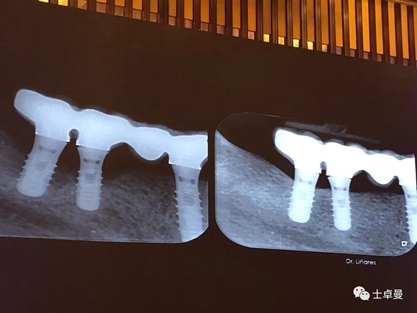

種植體周圍炎是影響牙種植遠(yuǎn)期效果導(dǎo)致種植失敗的主要原因之一。和天然牙一樣,如果口腔衛(wèi)生不良,菌斑滯留,那么細(xì)菌微生物就會對種植體周圍的軟組織不斷刺激,使機(jī)體產(chǎn)生炎癥反應(yīng),表現(xiàn)為黏膜的紅腫、探診出血甚至溢膿。也可通過X片來評估種植體周圍的骨量情況。

4、種植體周圍炎的治療

接下來Dr. Laurence Adriaens介紹了種植體周圍炎的治療,即非手術(shù)方式治療和手術(shù)方式治療。非手術(shù)方式治療提倡對患者進(jìn)行有效的口腔衛(wèi)生指導(dǎo),患者必須掌握有效的菌斑控制方法,以保持良好的口腔衛(wèi)生,還可以選用種植體專用的牙線清潔義齒鄰面及其周圍軟組織。同時應(yīng)養(yǎng)成每半年到一年定期復(fù)查,進(jìn)行專業(yè)清潔的習(xí)慣。

手術(shù)方式治療則需通過翻瓣清潔種植體及修復(fù)體上菌斑牙石,推薦在此過程中使用士卓曼鈦刷,因?yàn)樵撯佀⒉粫p傷種植體表面細(xì)微結(jié)構(gòu)。之后進(jìn)行植骨蓋膜來促進(jìn)種植體周圍吸收部分的骨的重建。